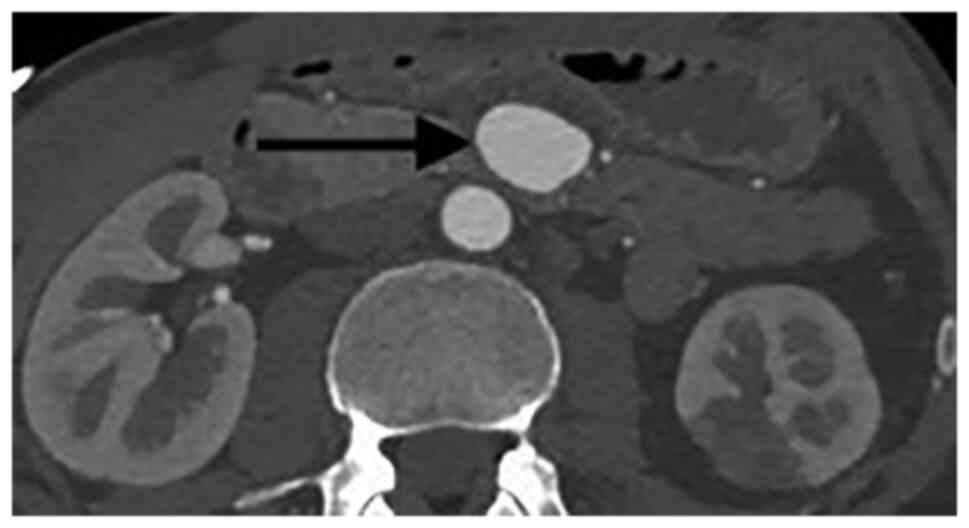

Visceral artery aneurysms are defined in this retrospective analysis as a true aneurysm in the celiac trunk (CT), superior mesenteric artery (SMA), inferior mesenteric artery, and/or their branches. Visceral artery aneurysms (VAAs) are rare and mostly asymptomatic., Rapid growth, size >2 cm, and pregnancy are risk factors associated with rupture. True visceral aneurysms are aneurysms are the result of weakening and thinning of the artery wall. Atherosclerosis, connective tissue disorders, infection (for example pancreatitis) and abdominal surgery are known risk factors for the development of VAA. Nowadays, conservative therapy, endovascular, and open surgery are the treatment options for patients with visceral aneurysms (VAA). During the last decade, endovascular repair of VAAs has been increasingly used (1-6). Catheter-based embolization or stent-graft placement are two major treatment options. Most VAAs originate from the splenic artery (SA) (60%) (Figs. 1 and 2), followed by the hepatic artery (HA) (20-50%) (Figs. 3 and 4). An origin from the superior mesenteric artery (SMA) (6%) (Figs. 5 and 6), the celiac trunk (CT) (4%) or other, smaller visceral arteries is considerably less common (7).

There were eight patients with an aneurysm of the SA, two patients with aneurysms of the SMA, one patient with an aneurysm of the HA and one patient with an aneurysm of the CT. Only one patient was symptomatic and presented with signs of bleeding. All patients received a contrast-enhanced CT-scan.

The median aneurysm diameter was 2 cm (range 1.5 cm to 5 cm) for all aneurysms, 3.75 cm for aneurysms of the SMA, 2 cm for aneurysms of the SA and for aneurysms of the CT and 1.5 for the aneurysm of the HA.